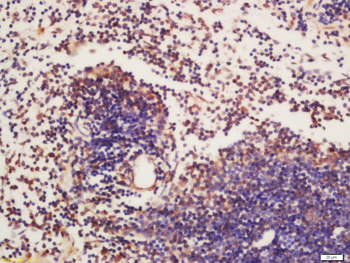

应用稀释比例:IHC-P=1:100-500, IHC-F=1:100-500, IF=1:100-500, Flow-Cyt=1ug/test, ELISA=1:5000-10000